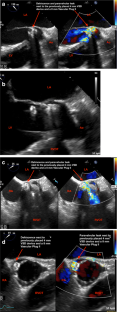

Fig. 4